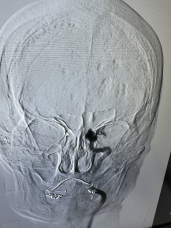

近日,广元市第一人民医院神经内科介入团队成功为91岁高龄患者实施急诊脑血管造影+机械取栓术,及时开通血管,改善了患者的症状。这是医院首次完成91岁超高龄老人急性脑缺血性卒中机械取栓术,老人术后恢复超预期,创造生命奇迹的同时,也再次彰显了医院卒中团队过硬的综合实力。

随即,卒中介入团队快速启动急诊手术流程。11:42,经介入治疗后,梁大爷闭塞血管顺利开通。再次造影显示,患者左侧大脑半球血流恢复。大脑在重新得到新鲜血液灌溉后,因缺血而不完全坏死的脑细胞逐渐恢复生机。